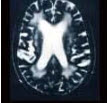

癫痫病理灶